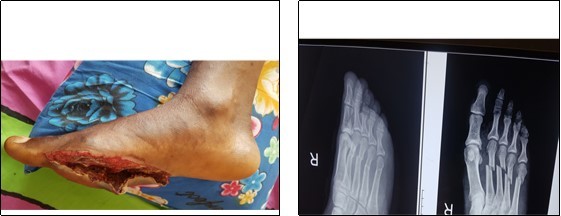

The open foot injuries in this study were treated by initial wound debridement followed by other procedures depending on the nature of the injury. Lacerations were debrided and sutured; where tendons were severed they were repaired as necessary, using standard repair methods. Open fractures were, after debridement, stabilized with K-Wires and thereafter, reinforced with a Plaster-of-Paris slab. Where skin defects could not be sutured, wound coverage was achieved by split skin grafting. None of the 81 patients studied required flap cover for a soft tissue defect. (Figure 1, Figure 2).

Figure 1.Open fracture of the shafts of the right 2nd, 3rd ,4th and 5th metatarsals, treated by normal saline irrigation, debridement and kirchner wire stabilisation.